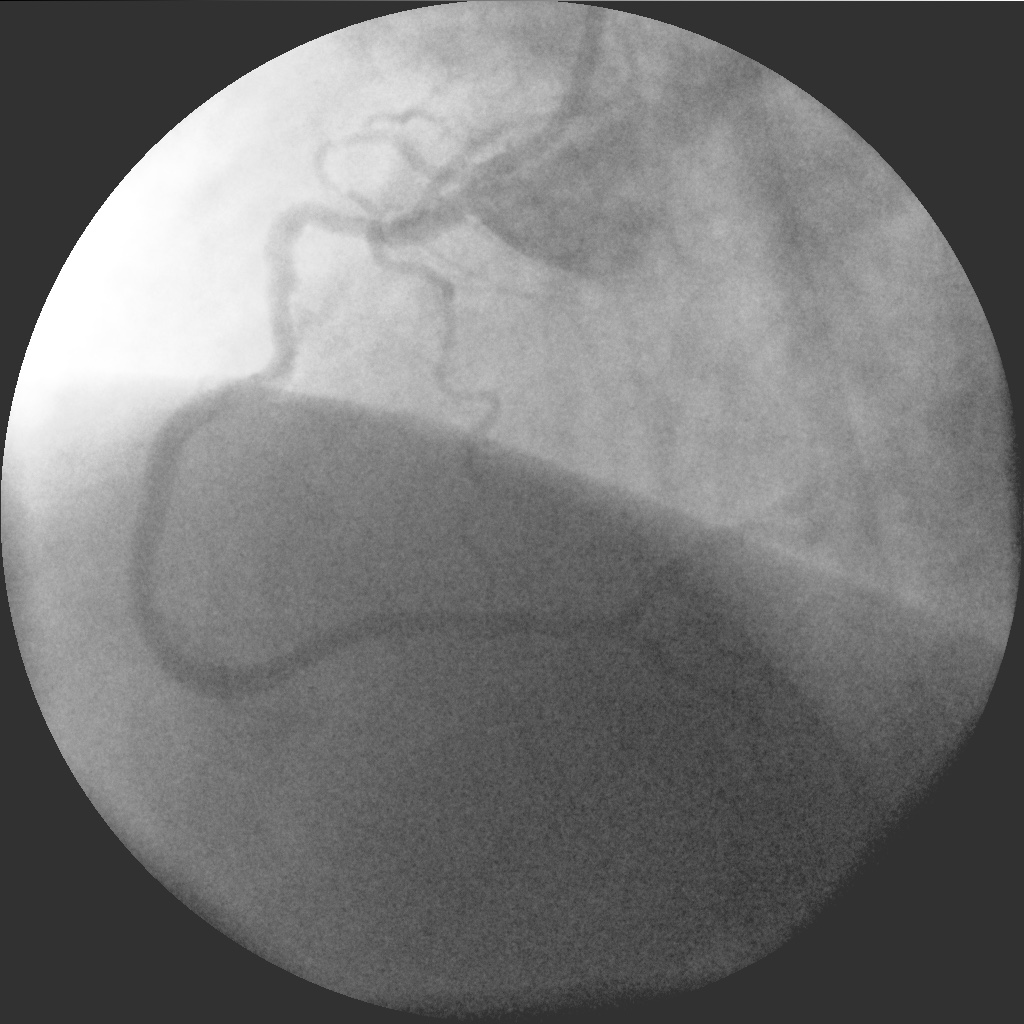

Пациент стентирован ПКА ургентно, ОИМ ЗСЛЖ

Комментарий к файлу: Стеноз ПКА

На снимке Вы видите уже рестеноз. Пациент обратился в клинику спустя два месяца от момента ургентной установки BMS-стента. Ухудшение состояния отмечал уже спустя месяц, маялся по поликлиникам пока не попал на повторную КВГ.